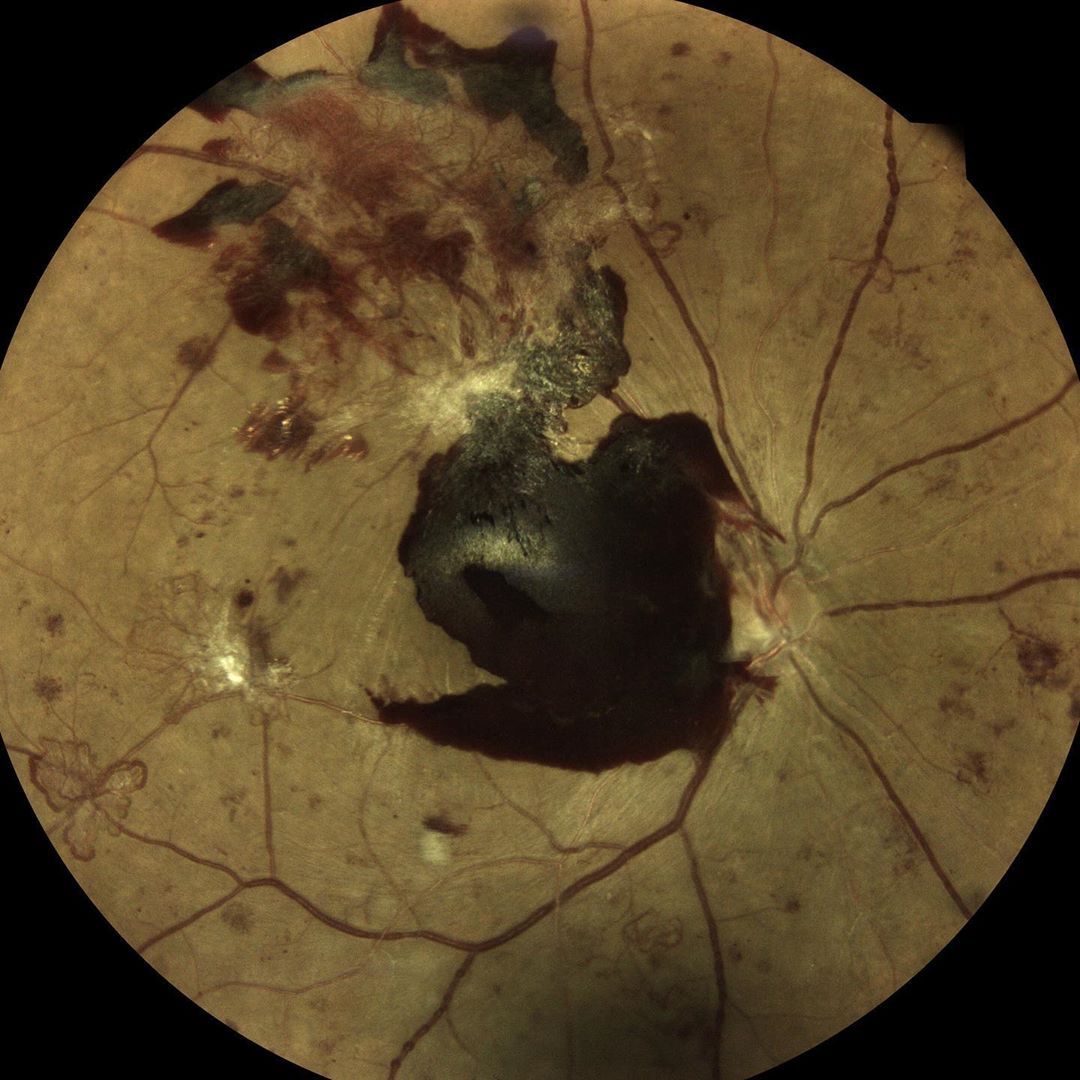

.@icare_usa released two new, next-generation imaging and tonometry devices: CenterVue DRSplus confocal fundus imaging system and

Icare ic200 handheld tonometer for portable measurement of IOP. buff.ly/2WwYbOi #optometry